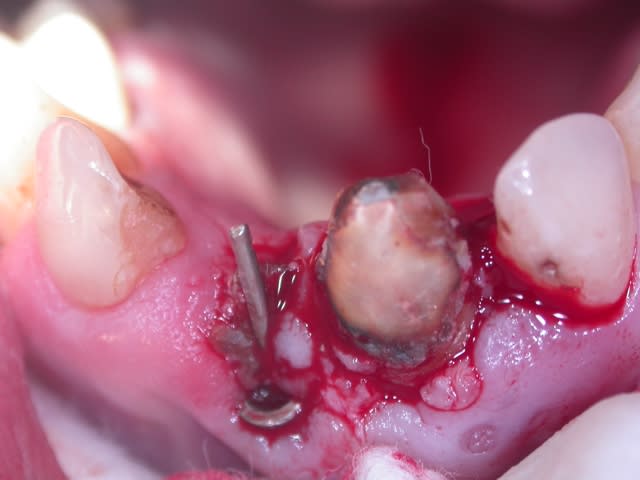

J'ai besoin d'un coup de main pour reconnaitre un implant qui a été posé sur un de mes patients (originaire de république tchèque).

Pour la partie "prothétique" bizarre je vous laisse commenté les photos.

Donc si quelqu'un reconnait le type d'implant et la marque à l'aide de la radio je l'en remercie.

marrant ton truc, c'est une sorte de prothèse aiguille sur implant.

Le mec a voulut coter un SC33 sur un implant je pense .

Il a du sceller la tige directement dans le fut de l'implant.